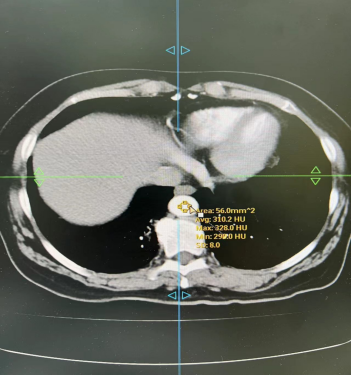

血管CTA:相同体重的患者 造影剂用320mg/ml和370mg/ml 都用4.0ml/s流速注射60ml对比剂

从上述图像可以看出,370造影剂明显比320造影剂CT值要高,显示要好